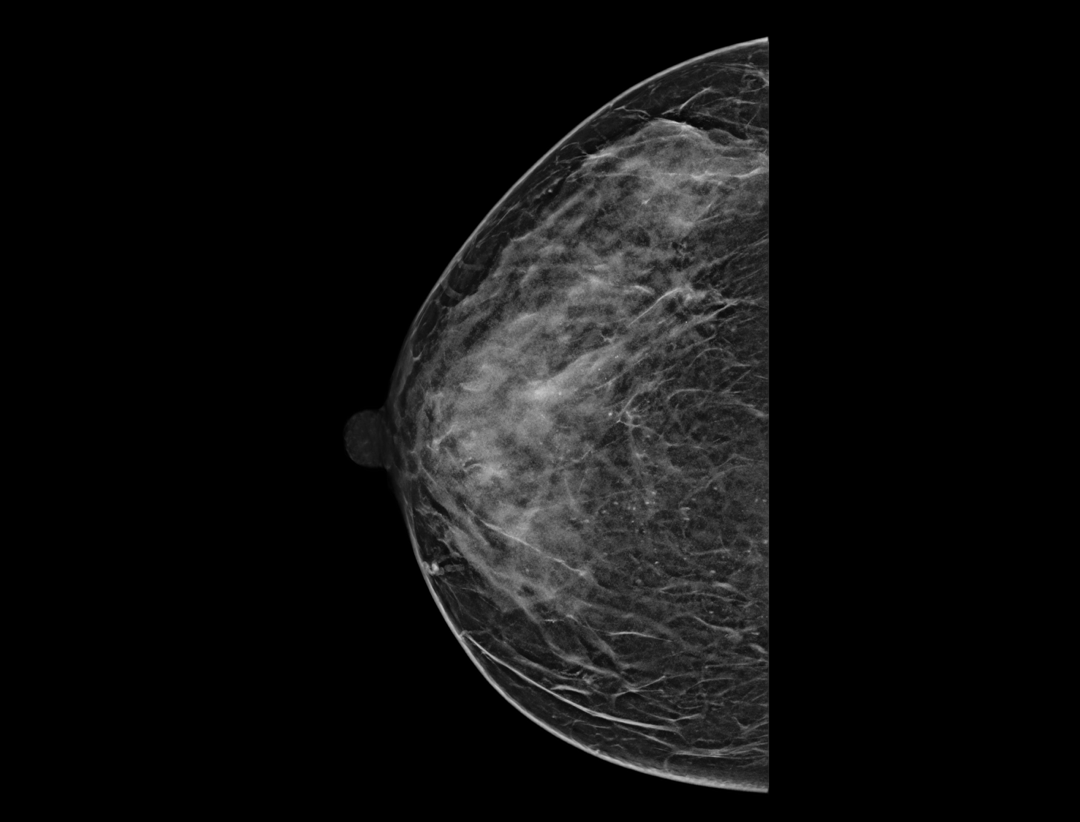

Adaptacyjne dostosowanie grubości warstwy tomosyntezy zapewnia szczegółowe obrazowanie przestrzenne zmian chorobowych i skupisk mikrozwapnień.

Wiele konfiguracji protokołów wyświetlania i wszechstronne narzędzia sprawiają, że przeglądanie mammografii cyfrowej jest bardziej elastyczne i uproszczone. Narzędzie lokalizatora pomaga użytkownikowi wskazać pozycje warstw tomosyntezy wewnątrz obrazu 3D.

Hybrydowe protokoły wyświetlania pozwalają na synchroniczne wyświetlanie obrazów 2D i warstw tomosyntezy w celu łatwego porównania. Dostępne są zarówno pogrubione warstwy (slabs), jak i widok płaszczyzny.